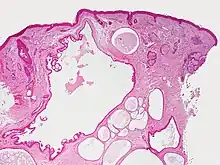

Hidrocystoma (also known as cystadenoma,[1] a Moll's gland cyst,[1] and a sudoriferous cyst[1]) is an adenoma of the sweat glands.[2]:787

Hidrocystomas are cysts of sweat ducts, usually on the eyelids.[3]:664 They are not tumours (a similar-sounding lesion called hidroadenoma is a benign tumour).

Hidrocystomas usually arise from apocrine glands. They are also called cysts of Moll or sudoriferous cysts. A type of hidroadenoma that arises from eccrine glands is uncommon.